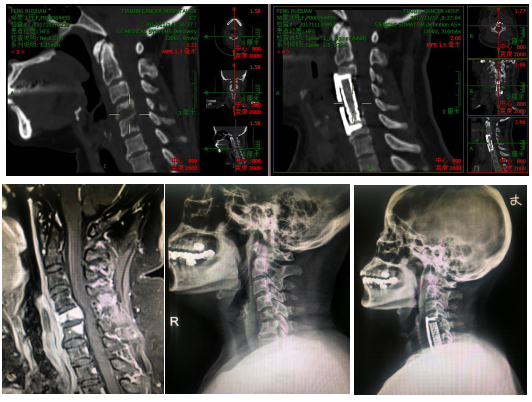

脊柱的承重功能是保持患者生存状态的关键,各种手术对脊柱骨结构的医源性破坏都会对脊柱稳定性产生负面影响,因此大限度减少医源性损伤和各种固定甚至重建技术在脊柱脊髓手术中发挥重要作用。对于良性神经鞘瘤等手术,可以采用半侧椎板切除、椎板切除复位固定等技术,对于骨转移癌姑息性后路减压患者可以钉棒固定来加固,椎体切除采用前路钛网钢板的内固定术,以及骨水泥充填术。